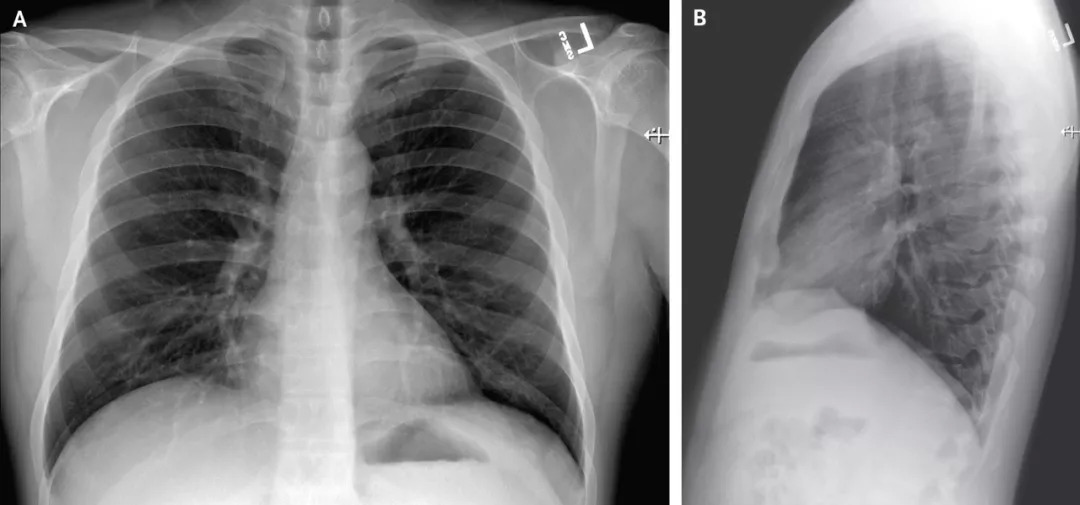

在医院第3天拍摄的胸部X光片未显示浸润或异常迹象(图三)。但是,从医院第5天晚上晚上进行的第二次胸部X光片显示,左肺下叶有肺炎的迹象(图四)。

图三

图四

这些影像学发现与从医院第5天晚上开始的呼吸状态变化相吻合,当时患者在呼吸周围空气时通过脉搏血氧饱和度测定的血氧饱和度值降至90%。在第6天,患者开始接受补充氧气,该氧气由鼻导管以每分钟2升的速度输送。

在医院第6天,第四次胸部X射线照片显示两个肺中都有基底条状混浊,这一发现与非典型肺炎相符(图5),并且在听诊时在两个肺中都出现了罗音。鉴于放射线影像学发现,决定给予氧气补充,患者持续发烧,多个部位持续出现2019-nCoVRNA持续阳性的情况,并发生了严重肺炎。

图五